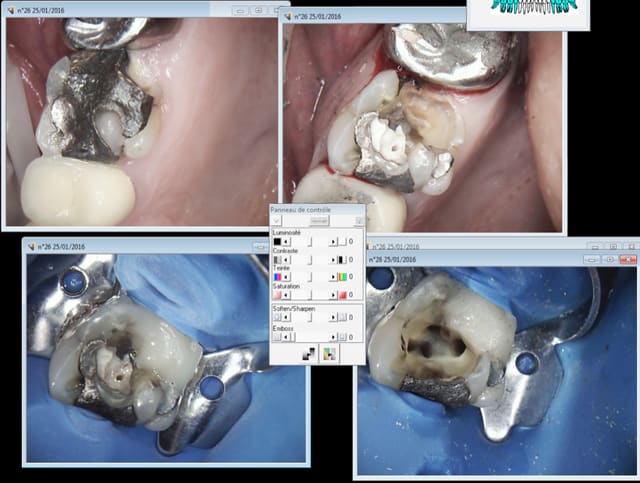

Encore du sur traitement ? dent a symptomatique. -)

Patient CMU je ne lui ai pas compté la reconstitution pré -endo, "parce qu'il faut bien faire quelque chose" le chicot finalement n'est pas si méchant que ca. -)